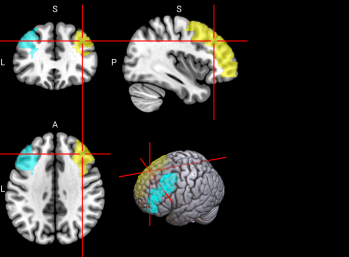

71,

72

L & R Precuneus (PCUN)

The precuneus is involved in recollection and memory, perception, episodic memory, and other cognitive processes [67].

/word/media/image16.png/word/media/image16.png